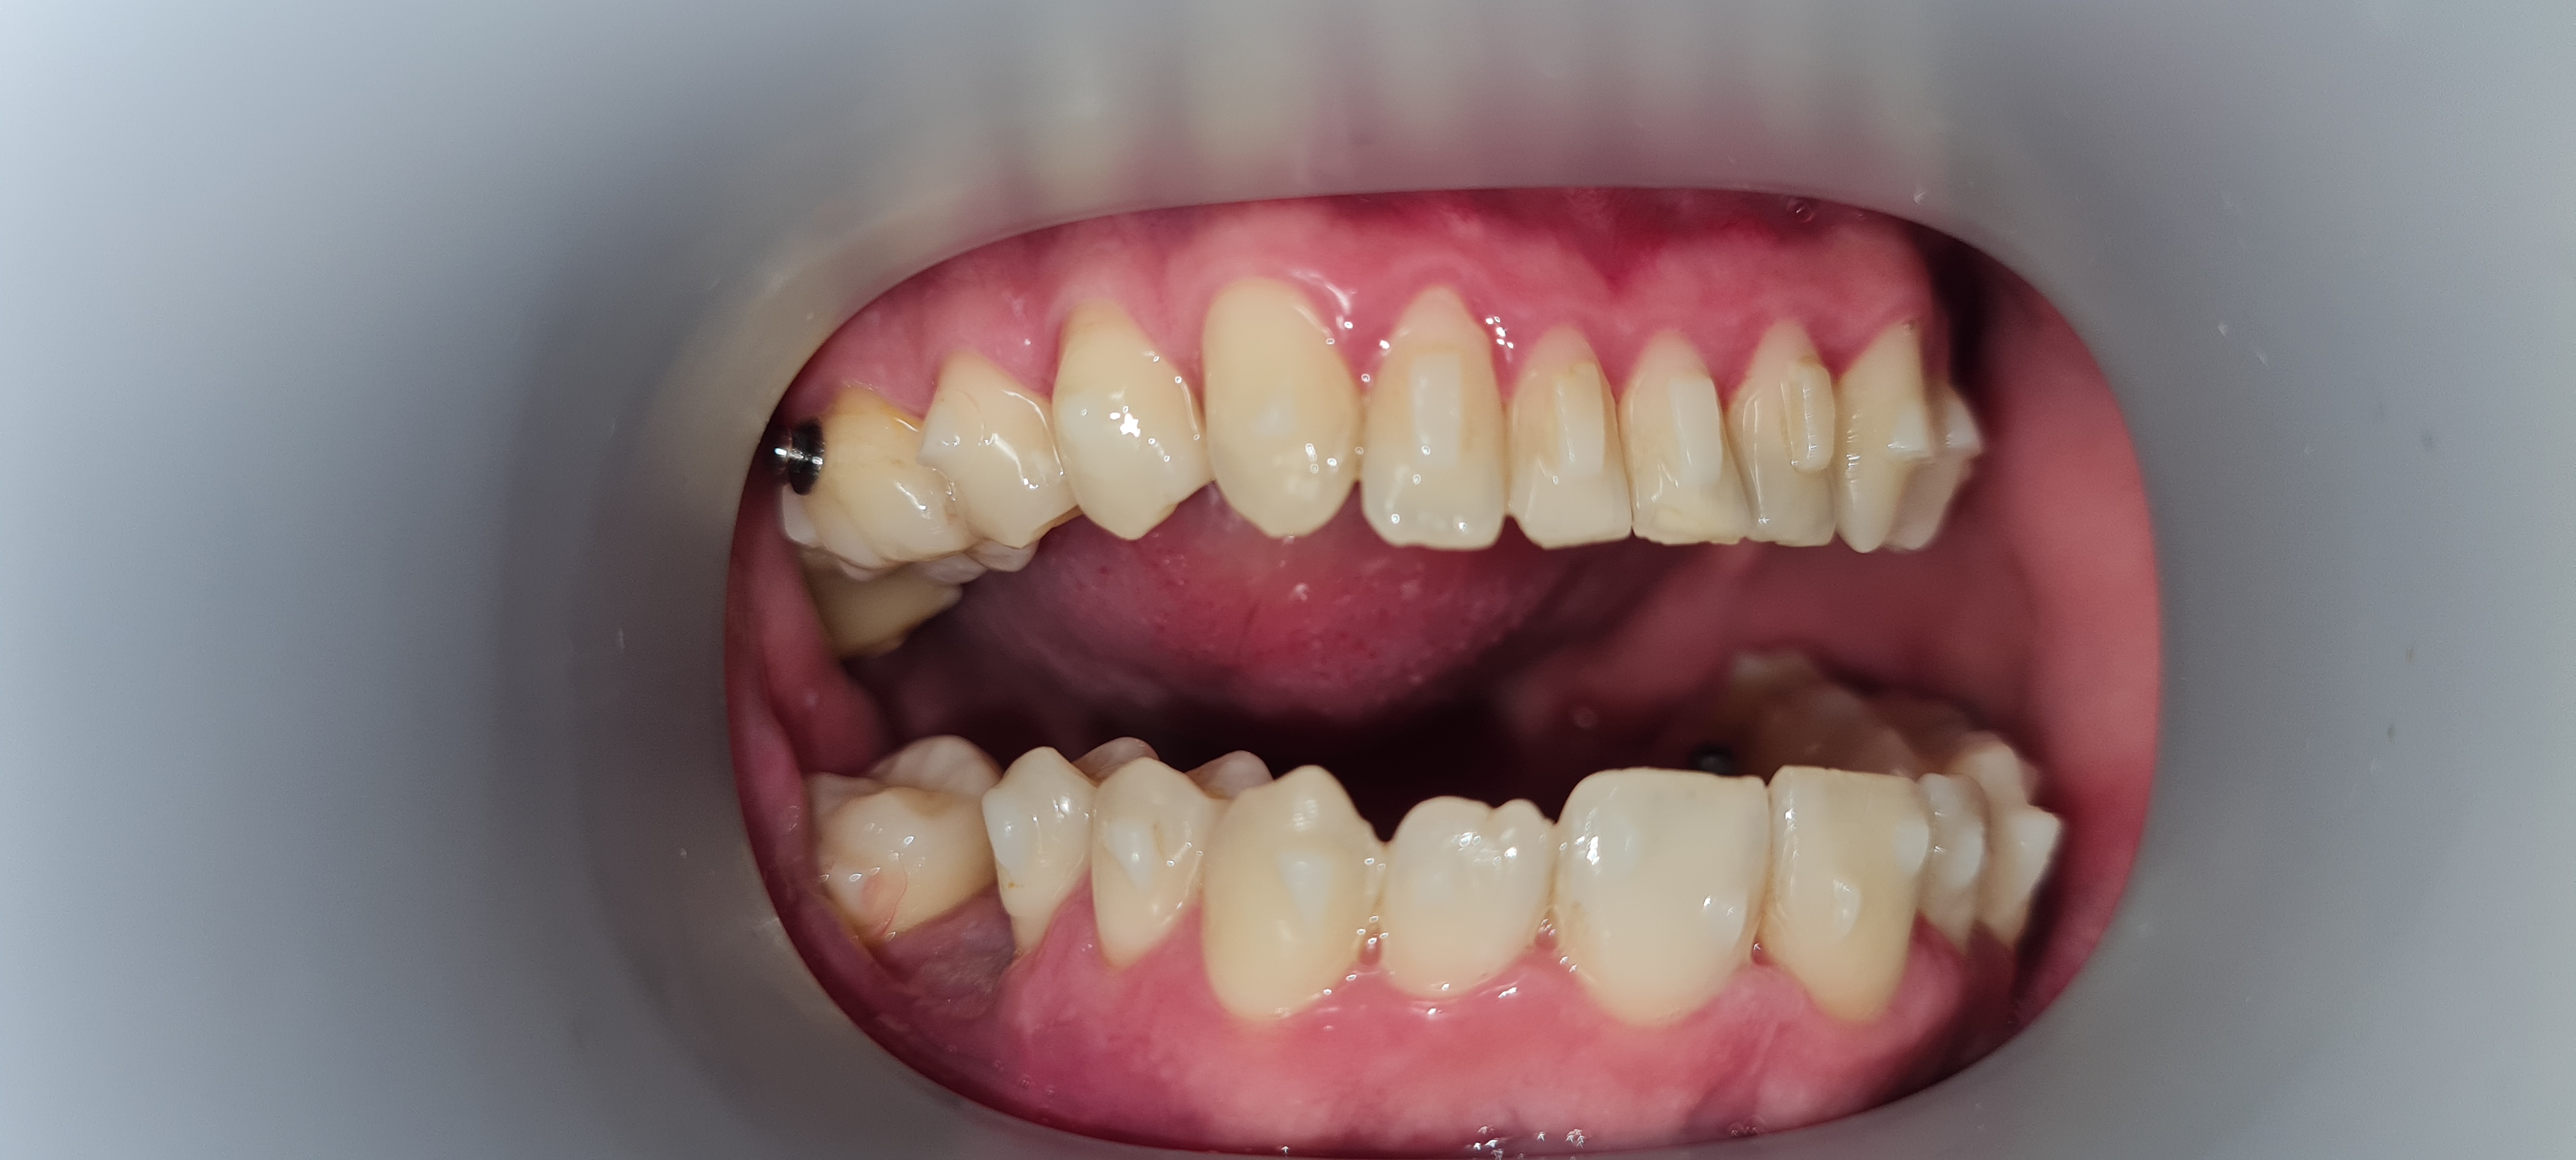

Po leczeniu nakładkami invisalign, będę zakładał korony na wszystkich zębach. Słyszałem, że po koronach nie będę musiał nosić retencji. Czy ktoś może się wypowiedzieć na ten temat?

#stomatologia #dentysta #invisalign #ortodoncja #protetyka

Pobierzdla mnie (nie jestem stomatologiem, ale raczej 99% stomatologów powie to samo) z tego co tu widać zakładanie koron na wszystkie zęby zakwalifikował bym do kategorii "samookaleczanie bez powodu". weź to jeszcze przekonsultuj zanim podejmiesz nieodwracalną decyzję która raz że będzie